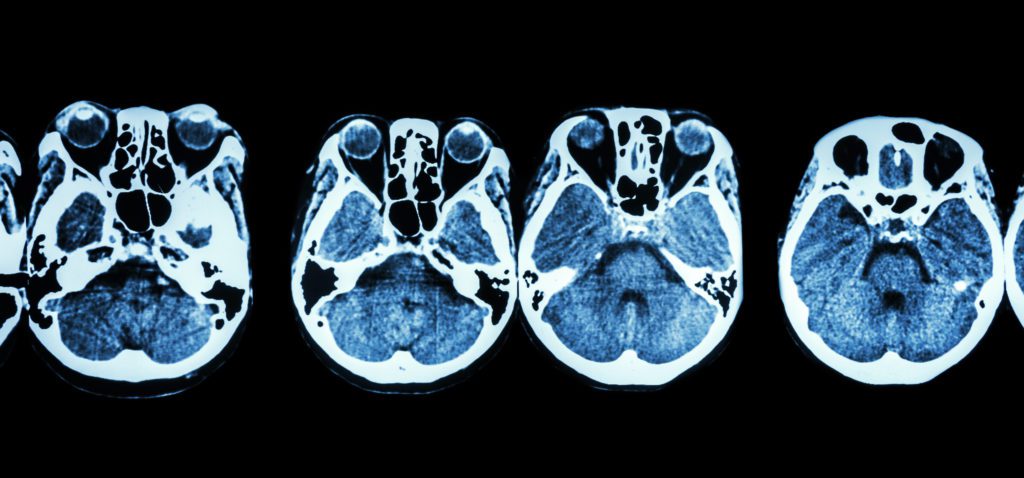

A sinus CT scan, or computed tomography scan, is a non-invasive diagnostic tool that uses a series of computer-processed X-ray measurements taken from different angles to produce cross-sectional images of the body.

Specifically, it focuses on your sinus areas. Unlike regular medical imaging, a CT scan provides a more detailed look at your sinus cavities, showcasing the bone, blood vessels, and soft tissue in and around these areas. This detailed view helps healthcare providers get a comprehensive understanding of the sinus structures and any abnormalities that might be present.

At an imaging center, a radiologist (which is a doctor specialized in interpreting medical images), analyzes your sinus CT scan. The radiologist examines the cross-sectional images for any signs of abnormalities in your sinus cavities. These could include blockages, inflammation, structural abnormalities, or growths like polyps. The images provide a detailed view, allowing the radiologist to observe even subtle changes in the sinus tissues.